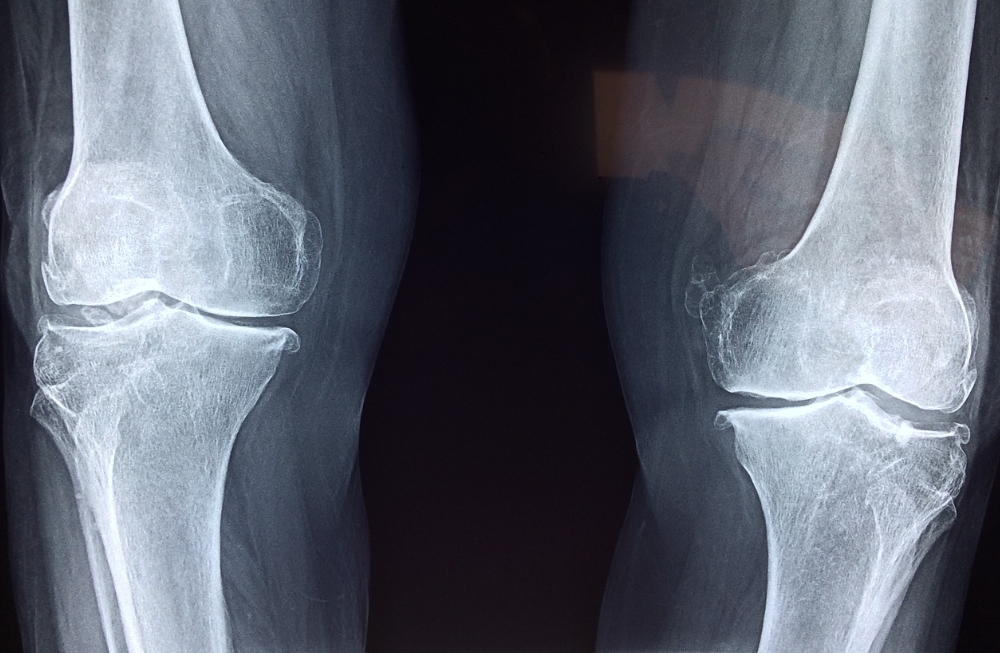

대부분의 뼈는 원형이 만들어진 후 그 일부분에서 뼈로 변화되는데 관절부위 만은 연골로 남아있다가 연골이 점차 뼈로 변화되는데 마지막에 남은 얇은 원판을 성장판이라고 하며, 이 성장판이 열려 있는지 닫혀있는지 여부에 따라 앞으로 키가 얼마나 더 클 수 있을지를 알 수 있습니다.

보통 성장판은 손목이 가장 빨리 닫힙니다. 일반적으로 성장판 닫히는 순서는 손목, 어깨, 팔꿈치, 무릎, 발목, 손가락, 발가락 뼈들입니다.

그러나 손목이 아닌 아직 다른 곳이 열려있다면 아직 키가 클 가능성이 충분히 있죠. 그중에서 최종키를 결정짓게하는 가장 중요한 성장판은 발목이나 무릎의 성장판입니다.